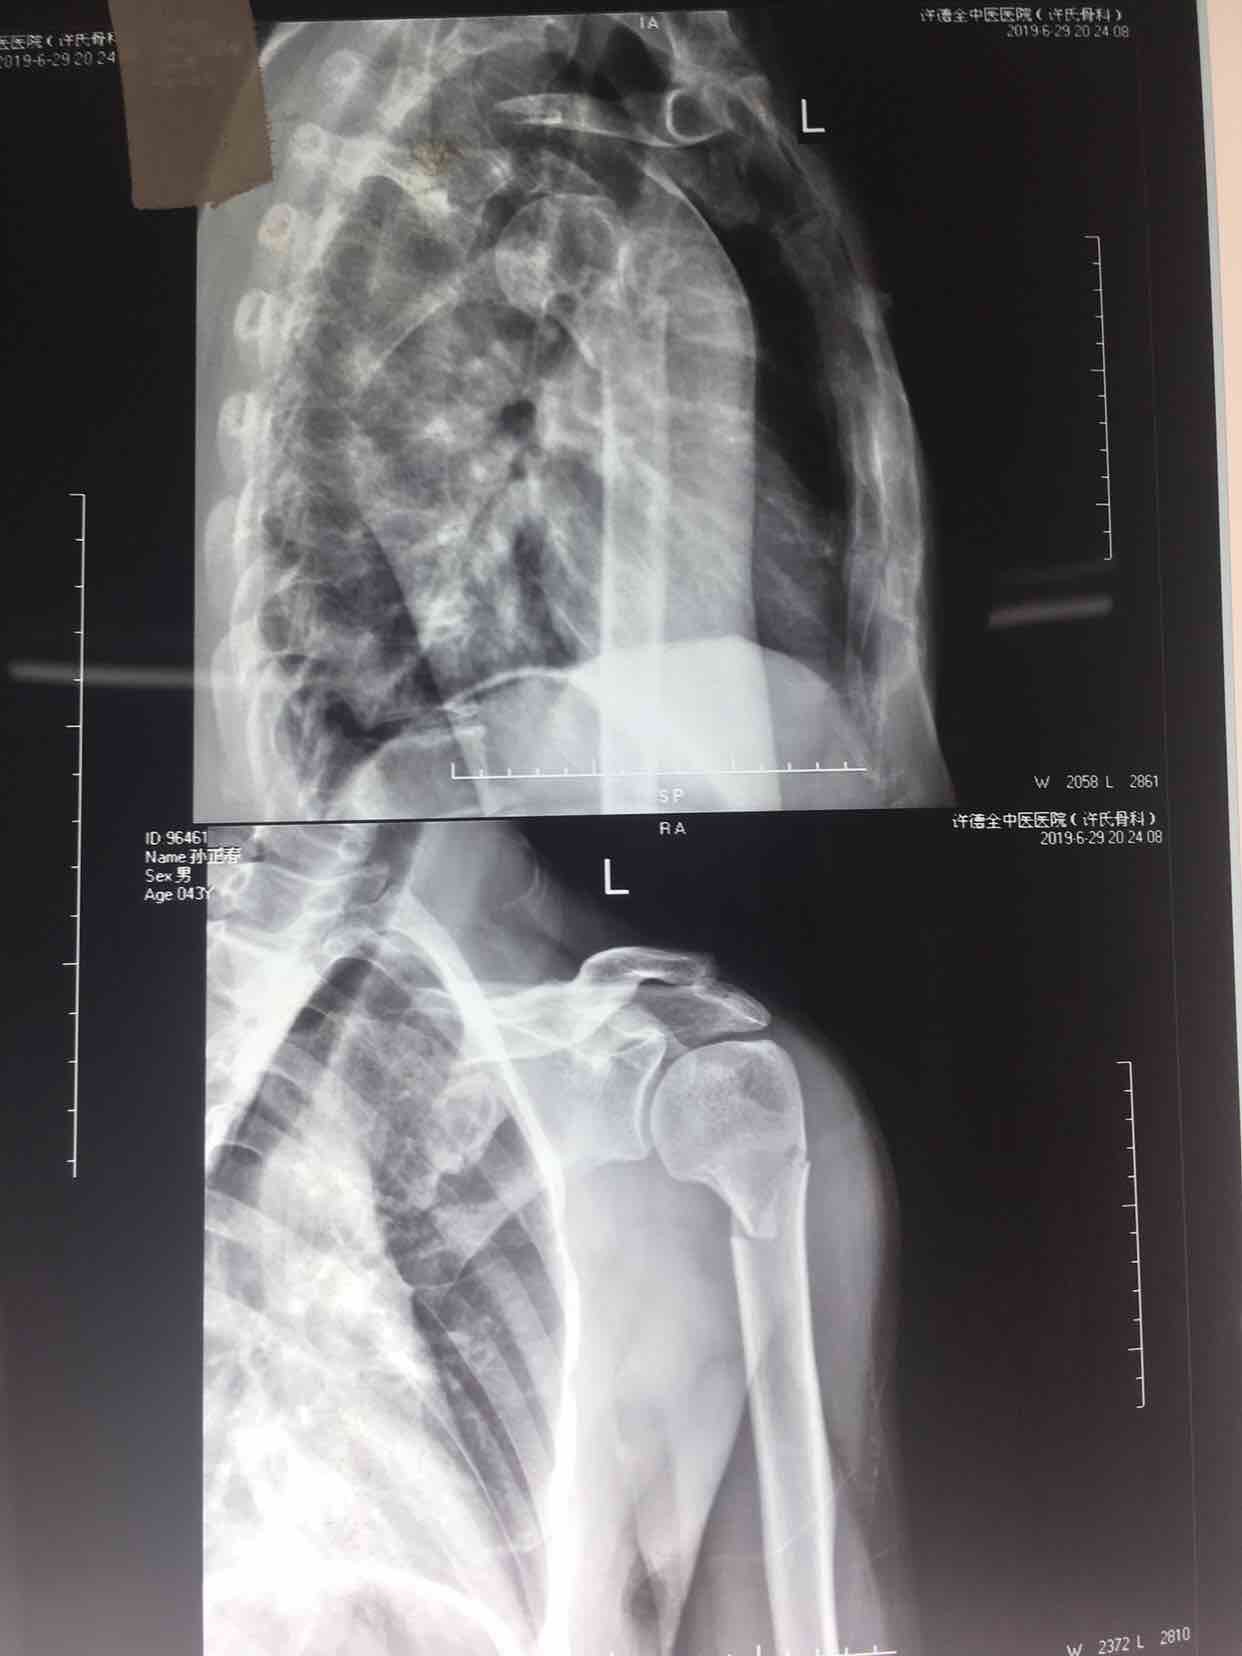

骨折 肱骨外科颈骨折

摔伤后左上臂肿痛,活动受限1小时入院。既往身体健康,无特殊不良嗜好。

生命体征平稳,心肺复未见异常。左上臂肿胀,畸形,局部皮色皮温正常,压痛及纵向叩击痛阳性,可及骨檫音或骨檫感,活动受限,末梢血运感觉正常。

诊断肱骨外科颈骨折在臂丛麻醉下行切复内固定术,术后抗炎,消肿止痛等处理。